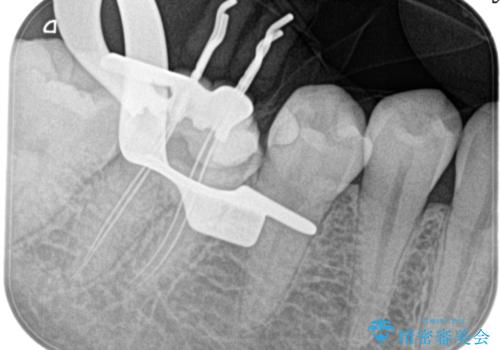

- 4日前から噛んだ時に痛むことを主訴に来院された患者様です。

歯髄壊死/症候性根尖性歯周炎の診断のもと、根管治療を行なっております。

根管治療は1回ごとにまとまった時間で治療を行うことにより2~3回の治療で完了します。

治癒不良の場合は外科的歯内療法の適応となります。